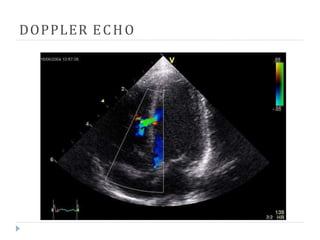

DOPPLER ECHO

An abnormal echocardiogram : Image shows a

midmuscular ventricular septal defect. The trace in the

lower left shows the cardiac cycle . Colors are used to

represent the velocity and direction of blood flow.